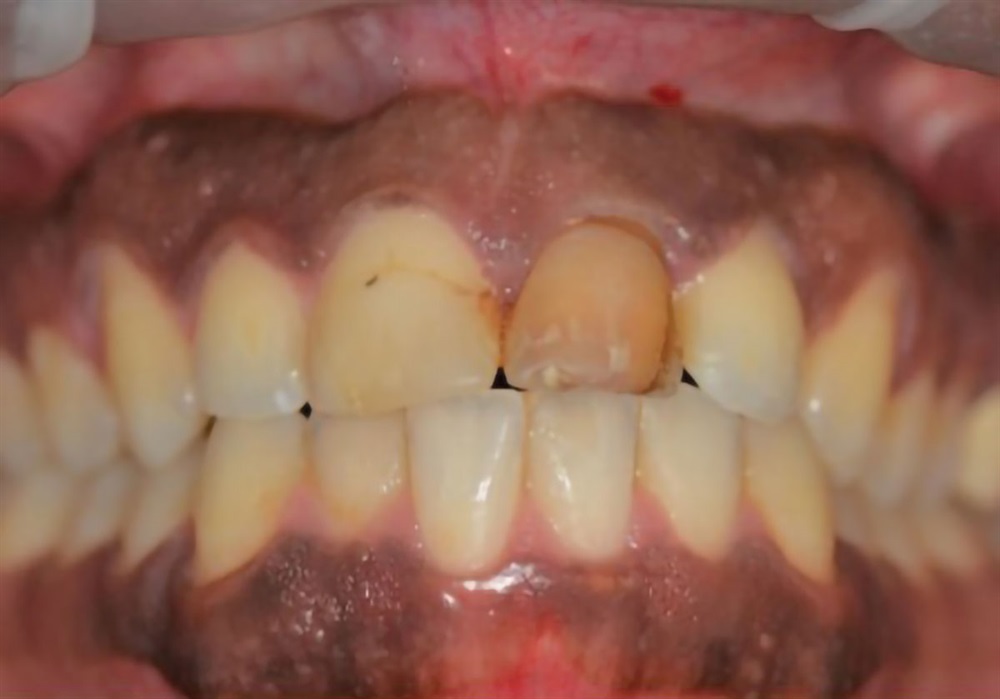

Before

Horton Favorite Case

This remains one of my favorite cases because it really displays the success one can have with anterior implant cases. I was using a modified “dual zone therapy” technique (developed by Drs. D.P. Tarnow and S.J. Chu), which I have found to have great utility in an office where making immediate provisionals does not fit the workflow.